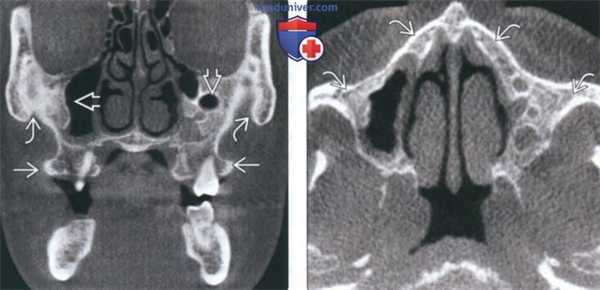

(Слева) При аксиальной «костной» КТ определяются классические признаки фиброзной дисплазии: выраженное вздутие левой верхнечелюстной пазухи с асимметричным выбуханием левой щеки, типичный вид «матового стекла». Обратите внимание на значительное уменьшение объема воздушной полости.

(Справа) При корональной костной КТ определяется фиброзная дисплазия с поражением правой нижней носовой раковины и латеральной стенки носа. Определяется выраженная экспансия раковины с изменениями в виде «матового стекла».

(Слева) При корональной «костной» КТ определяется экстенсивная фиброзная дисплазия орбит, петушиного гребня, решетчатой кости, среднего носового хода справа. Носовая перегородка отклонена влево.

(Справа) При аксиальной MPT Т2 в зоне фиброзной дисплазии определяется характерный выраженный гипоинтенсивный сигнал. Эти изменения типичны, когда наблюдаются совместно с «матовым стеклом» на КТ, и более диагностически значимы, чем гиперинтенсивные на Т2 очаги.